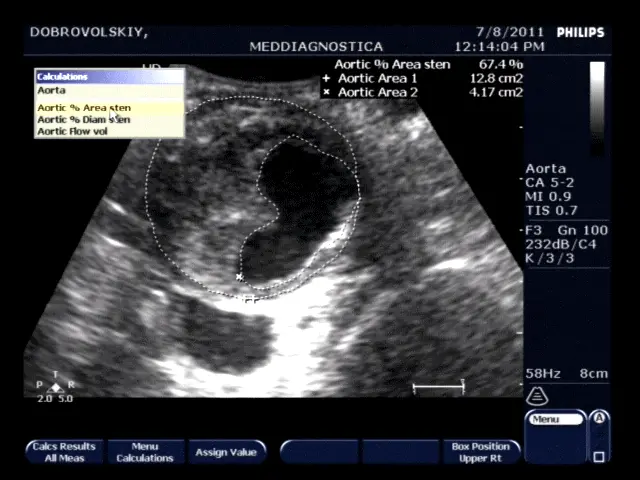

Метод дозволяє визначити наявність вільної рідини в черевній порожнині (кров, гній, серозна рідина), наявність збільшених лімфатичних вузлів, аневризматического розширення аорти, тромбозу нижньої порожнистої та ворітної вен, в ряді сумнівних випадків дає можливість підтвердити або спростувати діагноз гострого апендициту.